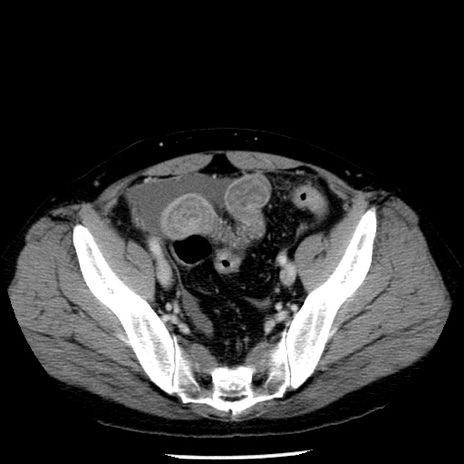

冠状断像

【症例】40歳代男性

【現病歴】2日前から胃痛あり。徐々に周期的な激痛に変化した。本日になっても激痛があるため受診。

【身体所見】意識清明、BT 38-39℃台あり、腹部:膨満、やや硬、右下腹部に圧痛あり。

【データ】WBC 8500、CRP 23.26